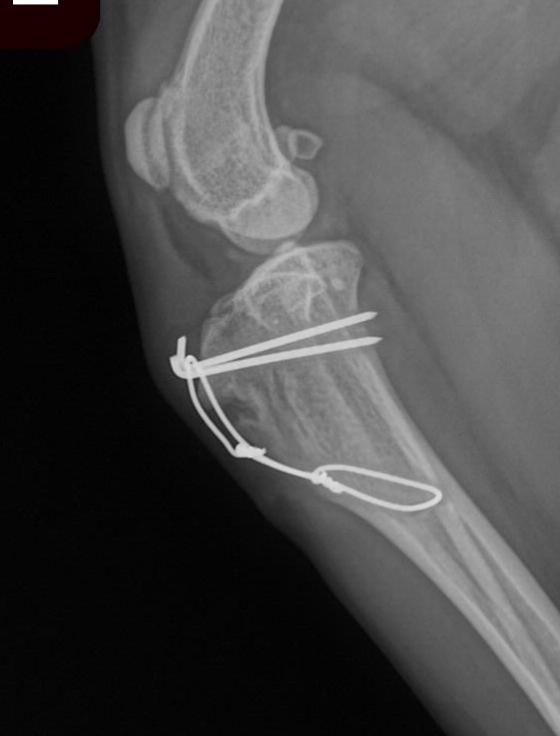

- Tibial tuberosity transposition

– The patella ligament attaches to the tibia at a point called the tibial tuberosity. This attachment point is often situated in a location medial to the centre of the joint, acting to pull the patella out of the groove. The tuberosity can be partially separated from the tibia and moved (translated) into a more lateral position. Putting the patella more in line with the groove. - Joint capsule release or imbrication

– More severe cases of patella luxation display a group of deformities of the bones which render the above techniques insufficient to properly correct the disease. In these cases, repair of the deformities via distal femoral osteotomy, proximal tibial osteotomy, or combinations of these techniques can be employed. Severely abnormal patellar grooves may require a technique called patellar groove replacement. - Concurrent cruciate disease

– Grade 3/4 and 4/4 are associated with a higher risk of concurrent Cranial Cruciate Ligament (CrCL) disease. It is not uncommon to repair both patellar luxation and cruciate ligament disease at the same time. The above techniques can be combines with TPLO or other geometry modifying procedures or with extra-capsular repairs to significantly improve the comfort and quality of life of these patients. One of Dr. Price’s areas of interest involves advanced stifle surgery. He brings a high level of care and experience to these cases and commonly applies the above techniques in combination to resolve complex cases of stifle disease.